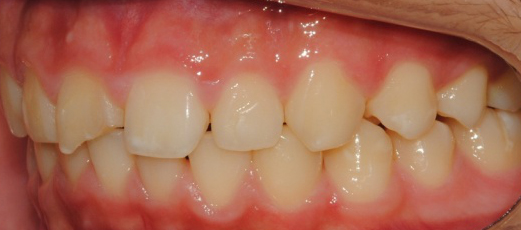

°ú°³±³ÇÕ°ú ¹«ÅÎ,ÅΰüÀýÀ» ÁÖ¼Ò·Î ³»¿øÇÏ¿© ÅμºÀå ¾ÇÁ¤ÇüÀåÄ¡¸¦ ÀÌ¿ëÇÏ¿© Ä¡·áÁßÀΠȯÀÚ·Î Ä¡·á½ÃÀÛ½ÃÁ¡ ±âÁØÀ¸·Î ÇöÀç ۰¡ ¾à 8cmÁ¤µµ ¼ºÀåÇÏ¿´½À´Ï´Ù. (Âü°í·Î 2³âÂ÷ ¿©µ¿»ý°ú ۰¡ 7-9cmŰ Â÷À̳²)